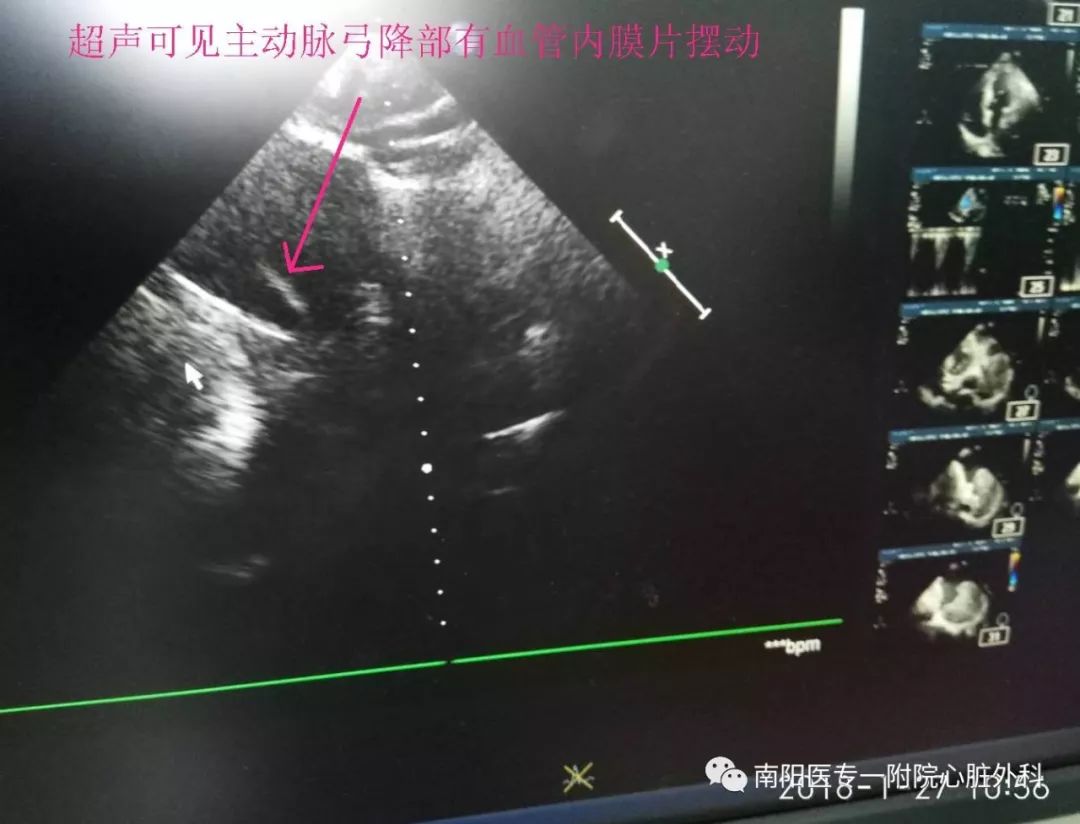

第三天来到我院胸外科住院,我科会诊时发现:患者突发胸背部疼痛,纵膈增宽,气管向右侧移位,声音嘶哑,胸腔积液,CT片上隐约可见降主动脉出现真假腔,高度怀疑主动脉夹层。

立即行CTA,明确诊断为Stanford B 型主动脉夹层,破口位于左锁骨下动脉根部,并且主动脉弓部明显增宽,左侧胸腔大量积液。此种情况非常危险,为主动脉夹层濒临破裂的征象,随时有发生破裂死亡的可能。

主动脉夹层(aortic dissection)是由于各种原因导致的主动脉内膜、中膜撕裂,主动脉内膜和中膜分离,血液流入,导致主动脉腔被分隔为真腔和假腔。典型的主动脉夹层可以见到位于真、假腔之间的分隔或内膜片。